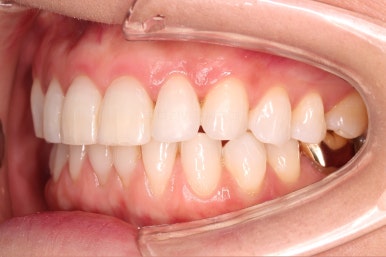

환자분이 원하시는 만큼 가지런해졌고, 부가적으로 생길 수 있는 부분들도 수용 가능한 선에서 잘 마무리가 되었습니다.

3개월이라는 빠른 기간 내에(심미보철 보다 약간만 더 긴 시간) 치아의 손상없이 마무리를 잘 했습니다.

물론 중간에 장치를 부착한 기간동안은 심미적으로 부담스러우셨겠지만요.

아래 앞니는 부분교정까지는 원하지 않으셔서 약간 다듬어 드리고 종료했습니다.